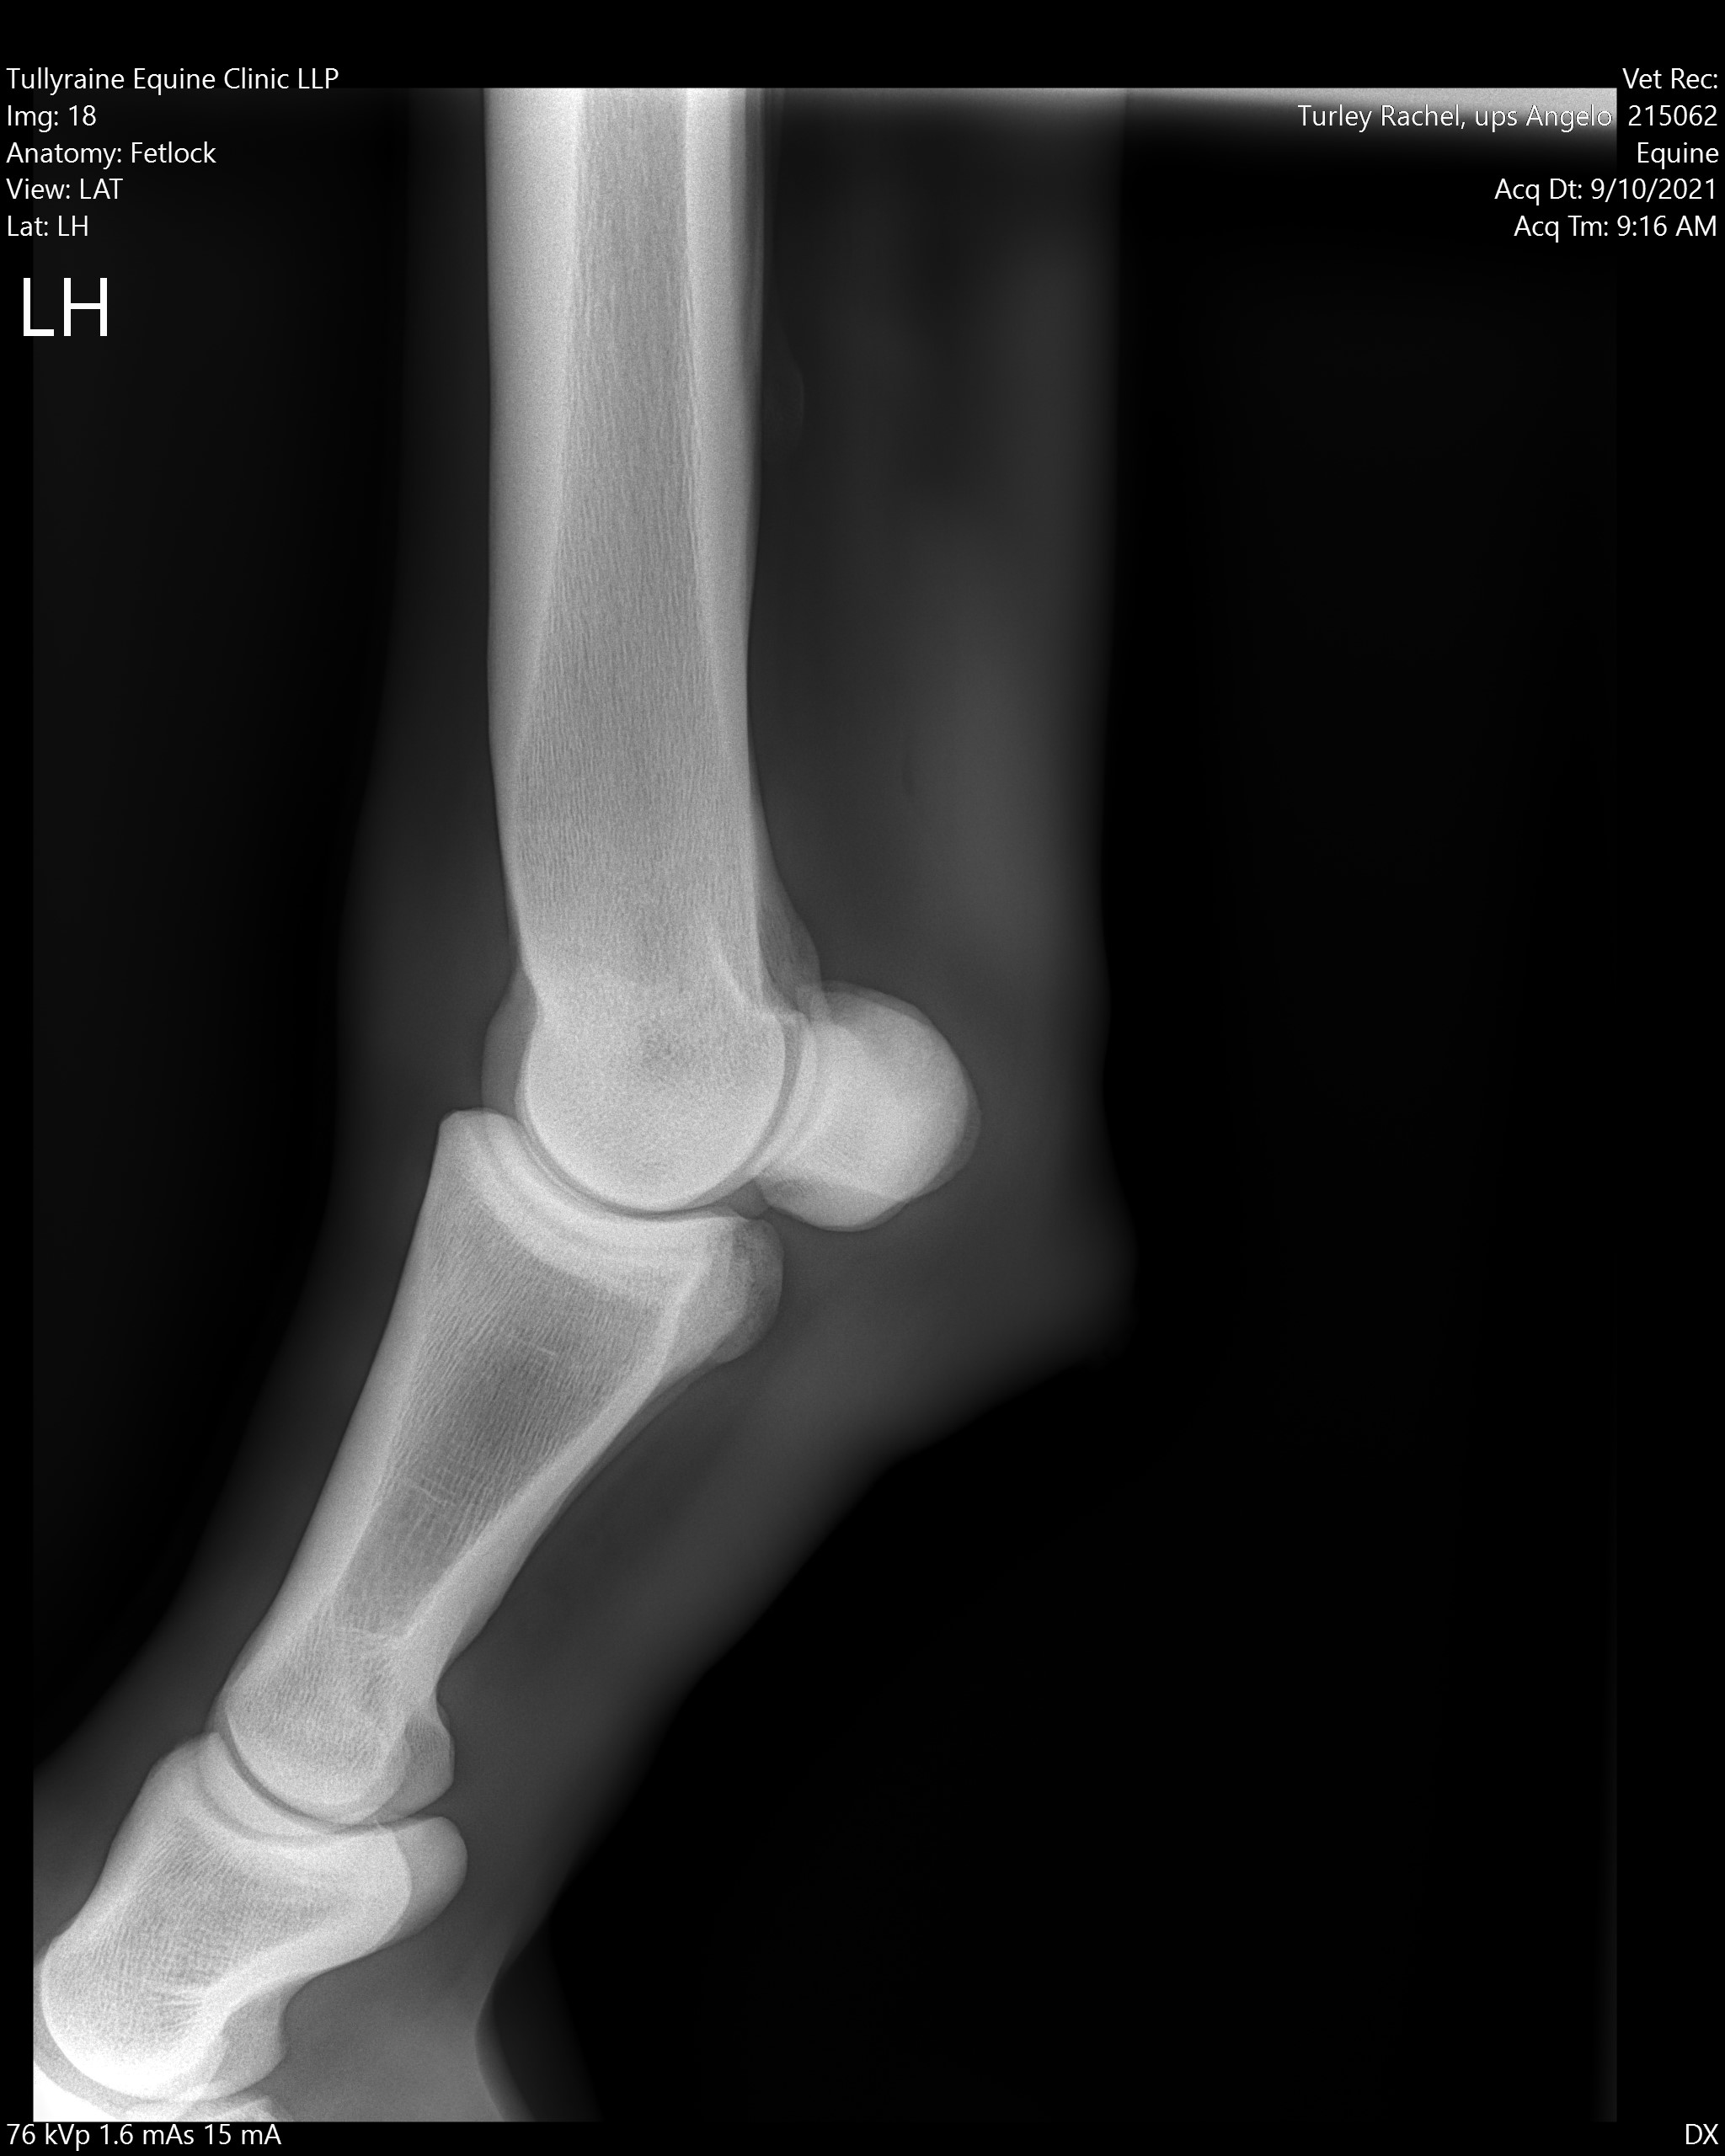

X ray horse

X ray horse 133 фото